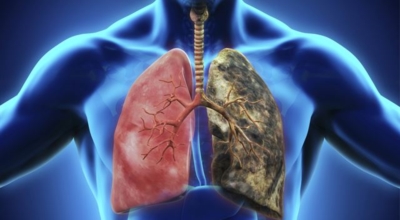

10. 폐에 좋은 음식 10 가지 - 율무

율무는 차가운 성질을 가진 식품으로 폐를 보호하고 정화하는 효능이 있습니다. 또 몸 안의 노폐물을 배출하여 부종을 줄여주고 흡연자의 경우 더 심한 가래를 줄여주고 니코틴 해독 효과가 있어 흡연으로 인해 나빠진 폐를 조금이라도 개선할 수 있게 도와주는 식품입니다.

폐에 좋지 않은 음식들을 멀리하여 폐에 무리를 주지 않는 것이 폐 건강을 지키는 것도 중요하겠죠? 트랜스지방 및 튀긴 음식들을 폐 건강을 악화시킬 수 있습니다. 튀김류의 음식들은 체내 염증들을 더더욱이 활성화시키며 유해한 활성산소의 생성을 증가시키기에 트랜스지방 및 튀긴 음식들은 멀리 하시는 게 좋습니다. 또한 가공육이나 설탕이 많이 함유되어 있는 음료, 기름 및 첨가 설탕이 많이 함유된 식품들도 좋지 않으니 참고하시기 바랍니다.